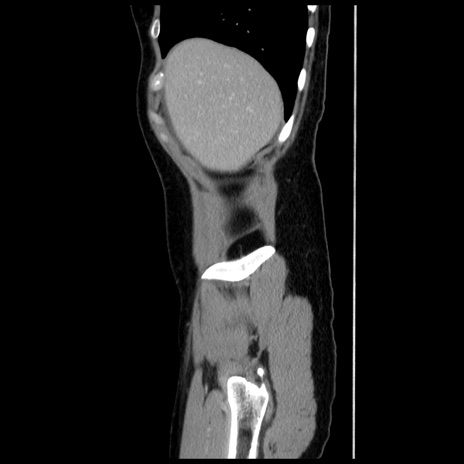

症例10(矢状断像)

【症例】 50歳代女性

【主訴】 腹痛

【現病歴】前日生レバーを食べた。今朝に排便あり。 昼前に突然発症の腹痛を生じ、当院救急外来を受診した。

【既往歴】 子宮筋腫にてで子宮全摘後

【身体所見】 意識清明、腹部:平坦、軟、下腹部やや左を中心に圧痛・反跳痛あり、筋性防御あり

【データ】WBC 7800、CRP 0.07